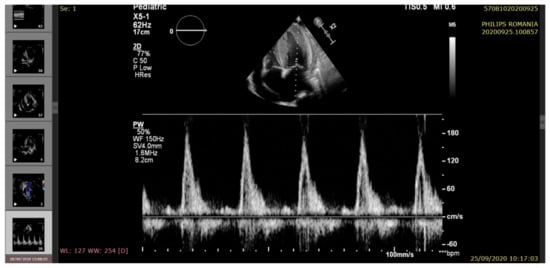

2. Case Presentation